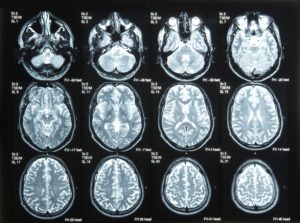

Dr. Musnick has 15+ years of experience in assessing and treating memory disorders, cognitive impairment, and early dementia